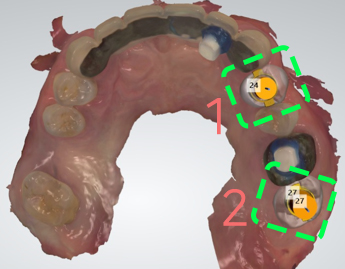

식립위치를 미리 결정한다.

어느 위치에 심어야 될 지 미리 예측을

할 수 있습니다.

미리 예측을 하니까, 심어서는 안되는 곳을

또 한번에 알아볼 수 있다는 말과 같습니다.

지속적인 수정이 가능

입 속에 심겨질 임플란트와 연결 될

보철의 형태등도 수정이 가능합니다.

구강 내에 시적을 한 이상에는,

직접법이라 해서 서로 불편한 상황이

펼쳐질 수 있으나

컴퓨터상에서는 구강 밖에서

수정작업이 이루어지는 간접법으로

볼 수 있기 때문에 서로 편합니다.